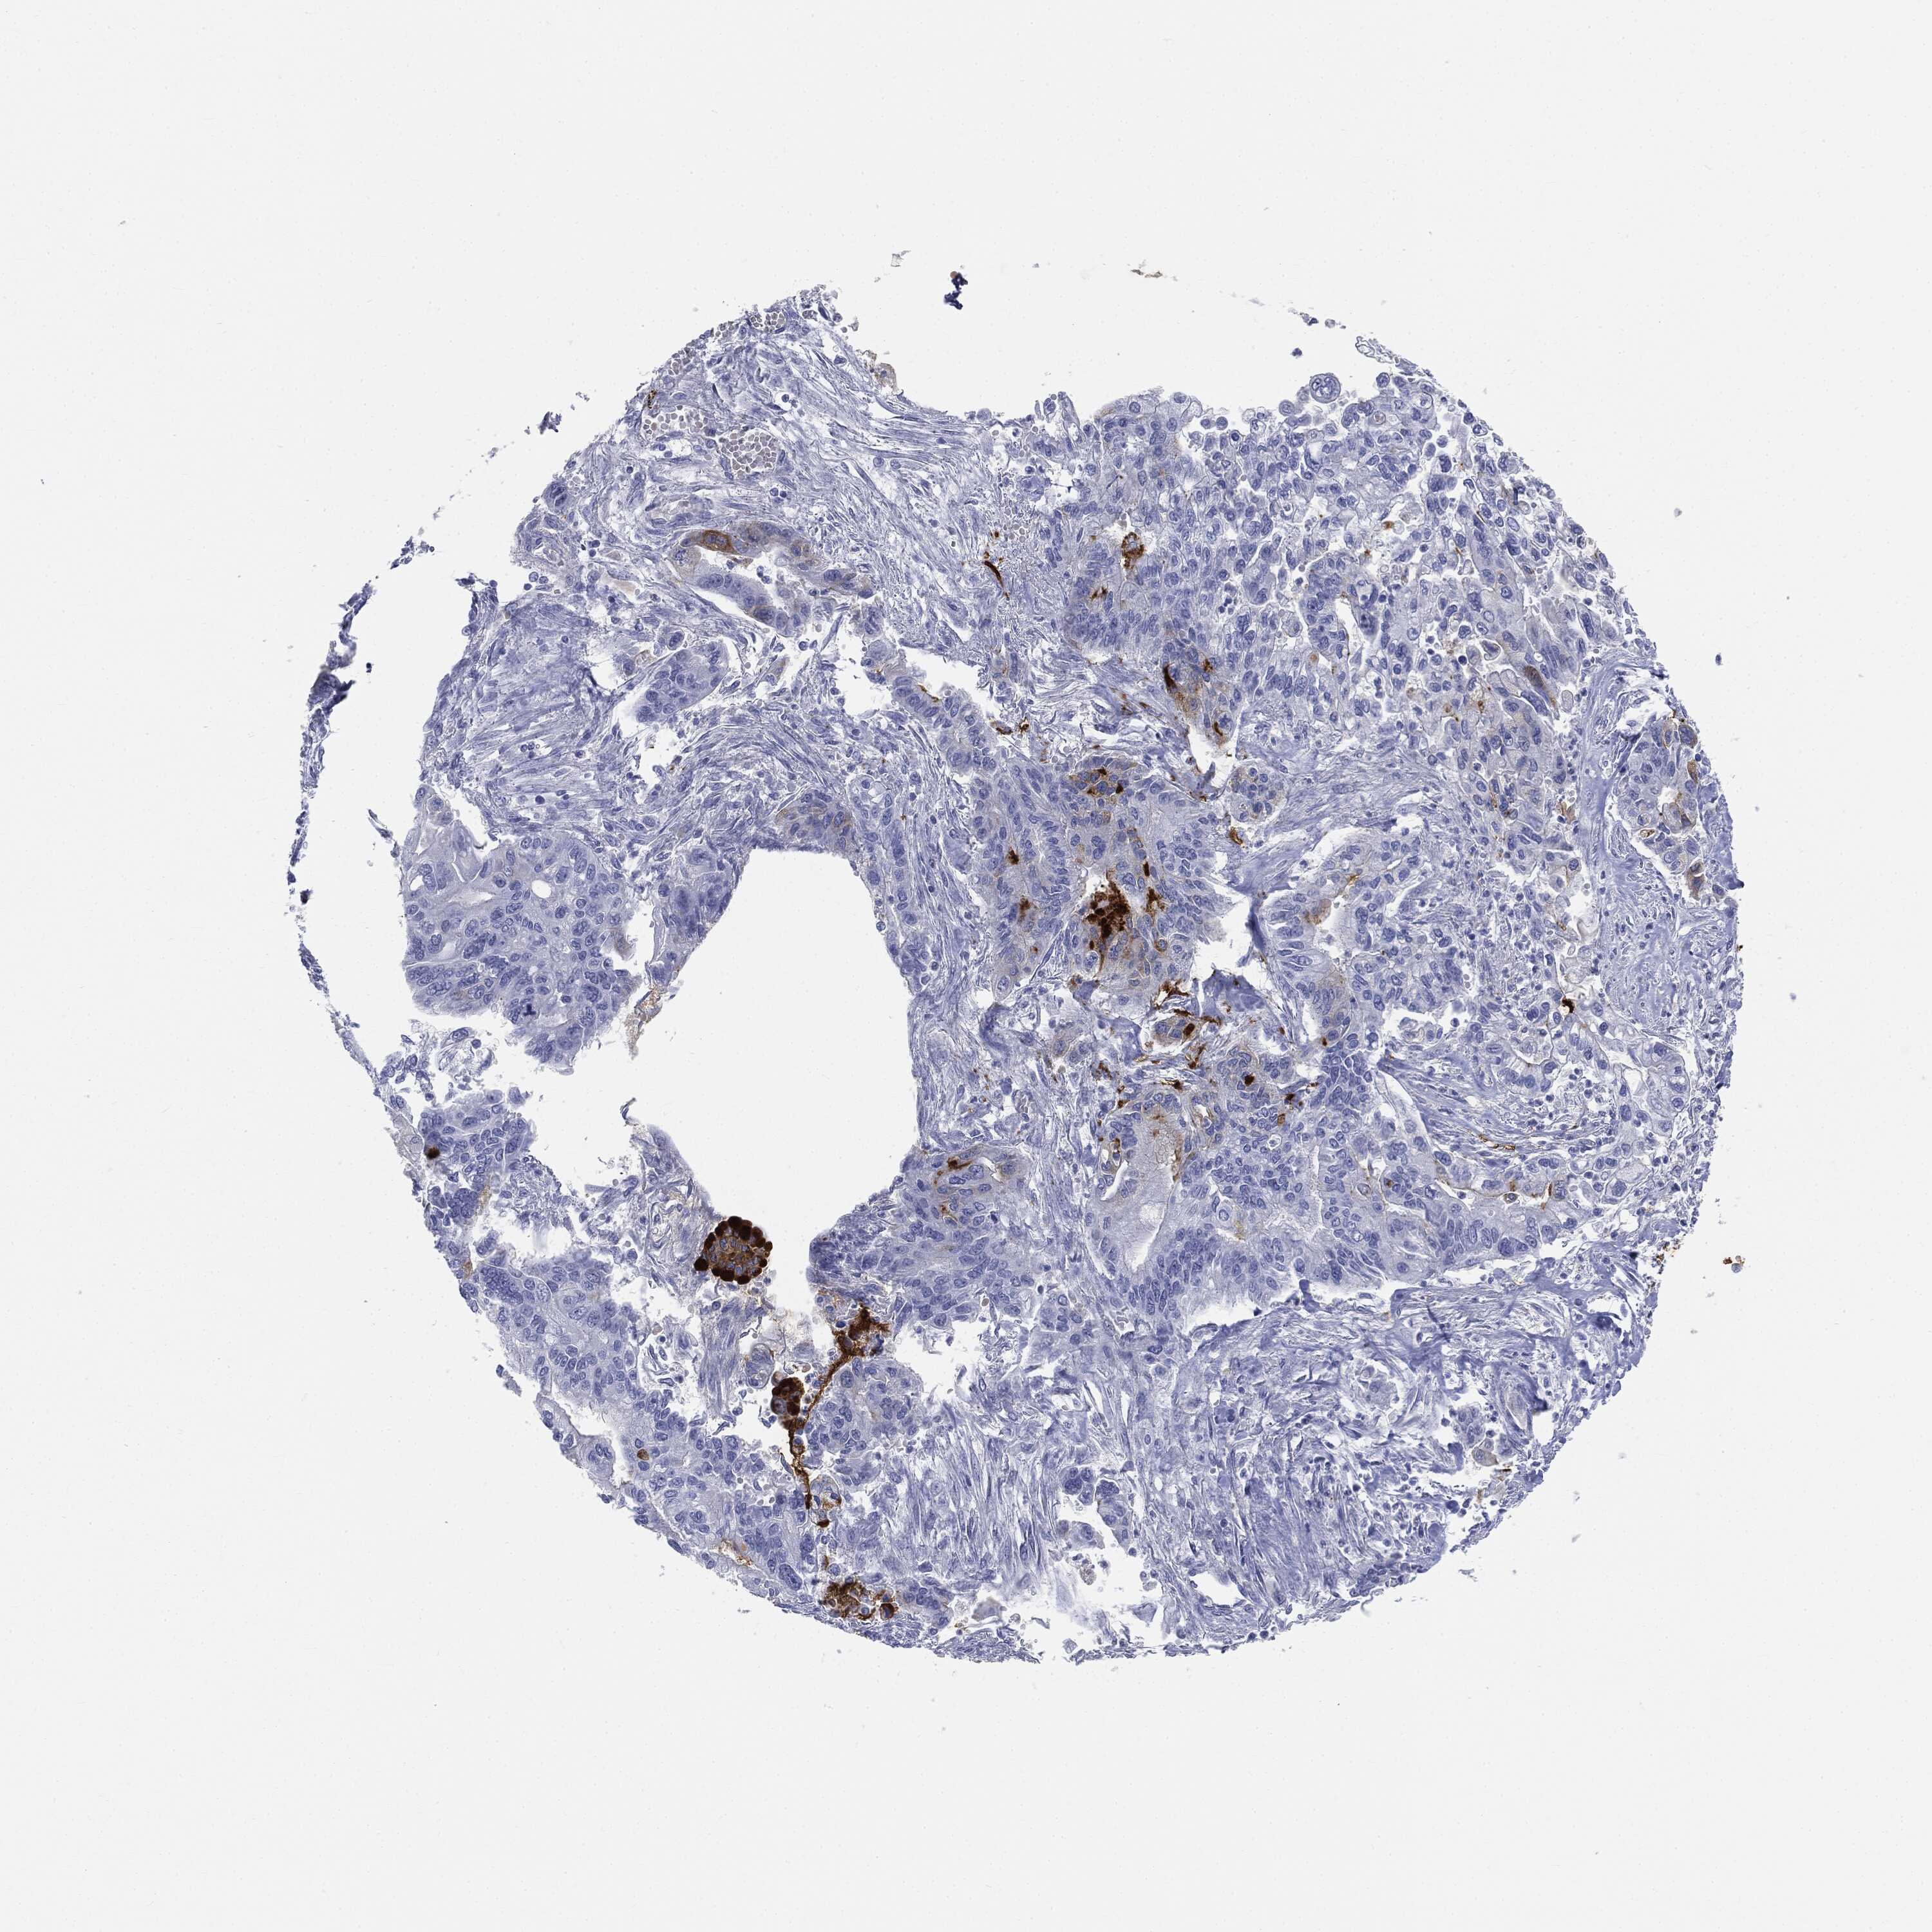

PANCREATIC CANCER - Protein expressioni

A mouse-over function shows sample information and annotation data. Click on an image to view it in a full screen mode. Samples can be filtered based on level of antibody staining by selecting one or several of the following categories: high, medium, low and not detected. The assay and annotation is described here.

Note that samples used for immunohistochemistry by the Human Protein Atlas do not correspond to samples in the TCGA dataset.

Antibody stainingi

Antibody staining in the annotated cell types in the current human tissue is reported as not detected, low, medium, or high, based on conventional immunohistochemistry profiling in selected tissues. This score is based on the combination of the staining intensity and fraction of stained cells.

Each image is clickable and will lead to virtual microscopy that enables deeper exploration of all samples and also displays staining intensity scores, fraction scores and subcellular localization as well as patient and tissue information for each sample.

HPA040615

HPA070378

HPA077637

CAB002774

CAB009395

Staining

High

Medium

Low

Not detected

Intensity

Strong

Moderate

Weak

Negative

Quantity

>75%

75%-25%

<25%

None

Location

Nuclear

Cytoplasmic/membranous

Cytoplasmic/membranous,nuclear

Adenocarcinoma, NOS

Adenocarcinoma, metastatic, NOS